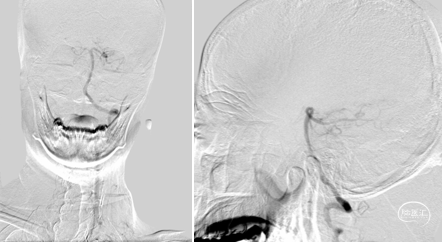

术前造影,BA近端闭塞。

术前造影,LC7次全闭塞。

术前造影,RICA 通过交通动脉向左侧颈内动脉及基底动脉尖代偿供血。